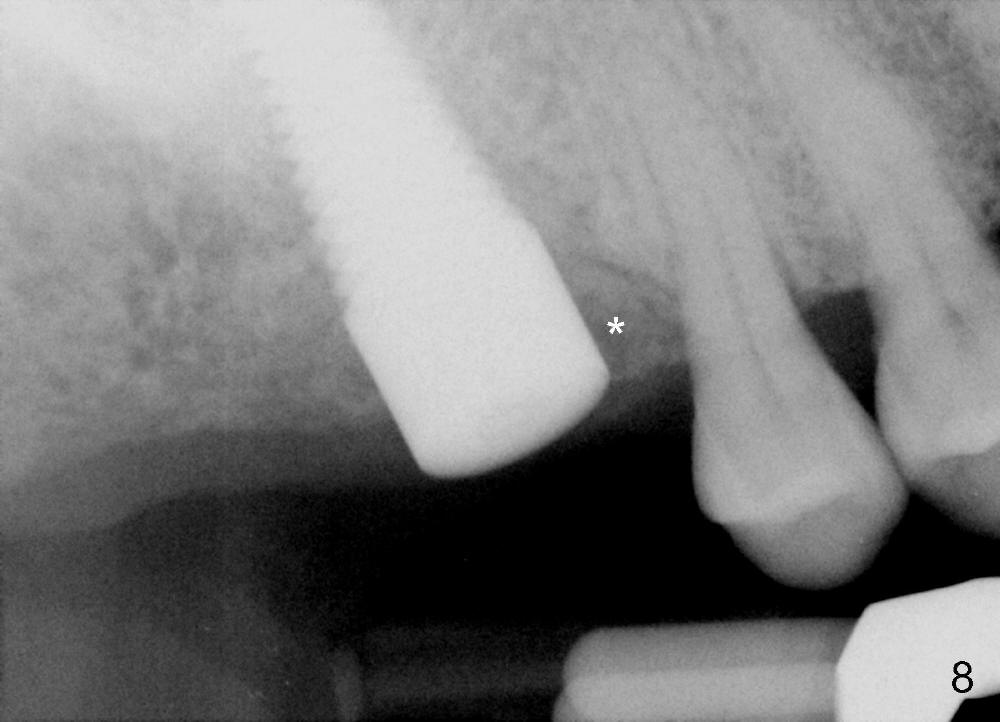

The upper right 1st molar fractures, the lingual portion mobile (Fig.1). There are deep pockets mesiolingually and distolingually. Fig.2 is preop PA, showing mesial bone resorption (*). The 84-year-old lady agrees extraction and immediate implant. Extraction is difficult due to not only root fracture but also hemorrhage. Following debridement of granulation tissue, the 3 sockets are packed with gauze for hemostasis. Even so, there is oozing from the bone. The septum can not be seen clearly. Its position is determined by an explorer. Osteotomes have to be used for osteotomy in the septum, followed by taps. The first intraop PA shows that 5x20 mm tap penetrates the sinus floor (Fig.3 ^). The osteotomy is further enlarged until 7x17 mm tap with stability (Fig.4). So far there has been no sign of sinus membrane perforation. Mixture of freeze dry mineralized bone and Osteogen is placed in the socket and pushed to the buccal and lingual walls as well as into sinus using a 4 mm flat end osteotome. A 7x17 mm implant is initially difficult to be inserted possibly due to blockage by bone graft. The osteotomy have to be recreated by a series of osteotomes and taps before placement of the 7x17 mm implant. It appears that the apical threads have been engaged into the sinus floor for primary stability (Fig.5). The insertion torque is 40 Ncm. According to our experience (1,2), this is not enough; finally the torque is increased to 60 Ncm by turning the implant more apically. The large implant obliterates the socket mesiodistally; the buccal and lingual gaps are filled with bone graft, followed by a collagen membrane (Fig.6 *) and suture. In order to protect the membrane, a short abutment is placed (A) and perio dressing (Fig.7*) is placed without occlusal interference. The abutment is removed 1 month postop, as the perio dressing has been dislodged. The patient returns for restoration 8 month postop. Bone regeneration occurs apparently in the coronal aspect of the implant (Fig.8), especially mesially (*, as compared to Fig.5). The gingiva-level implant is slightly subgingival mesially (Fig.9 M), probably due to high placement (compare to Fig.6). There is no bone resorption 6 months post crown (Fig.10 C) cementation.